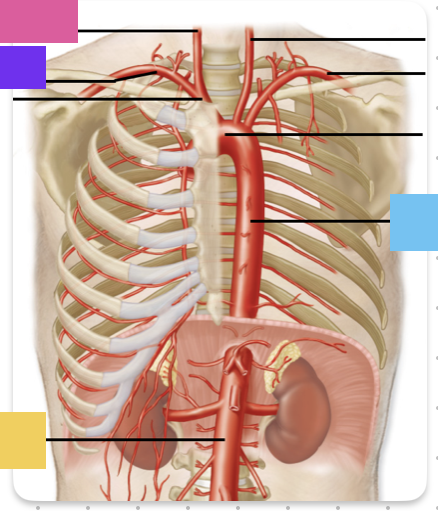

ascending aorta

aortic arch

brachiocephalic trunk (blue)

right common carotid artery

right subclavian artery

left common carotid artery (grey)

left subclavian artery (black)

descending aorta

thoracic aorta

abdominal aorta